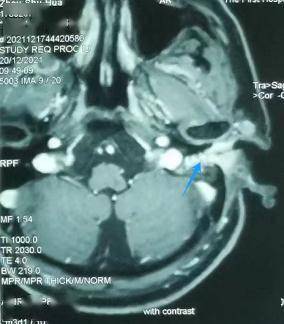

颞骨MRI:左外耳道肿物(蓝色为肿瘤)